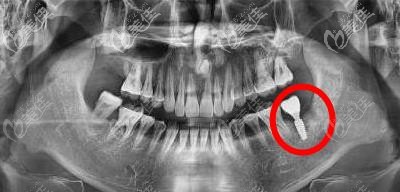

醫(yī)生會(huì)根據(jù)X光片或者是三維CT影像來評(píng)估患者種植區(qū)的牙槽骨量,如果牙槽骨吸收的不多,通常可以通過添加骨粉來增加骨量。但如果牙槽骨吸收過多,造成了骨寬度或者高度不足,往往需要通過植骨、骨擠壓、上頜竇提升等前期手術(shù)來增加骨量,從而達(dá)到種植的要求。